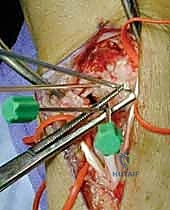

2. النهج الجراحي (The Approach)

يتم إجراء شق جراحي ظهري (من خلف الرسغ). هنا تتجلى مهارة الدكتور هطيف في تحديد وحماية العصب الكعبري السطحي (SRN) والأوردة الحيوية. يتم فتح محفظة المفصل (Capsulotomy) بعناية فائقة للوصول إلى العظام الرسغية.

4. الرد التشريحي للعظام (Anatomic Reduction)

هذه هي الخطوة الأكثر حساسية. باستخدام أسلاك كيرشنر (K-wires) كـ "عصي تحكم" (Joysticks)، يقوم الدكتور هطيف بتصحيح تشوه DISI. يتم تدوير العظم الزورقي للخلف (تمديد) وتدوير العظم الهلالي للأمام (انثناء) حتى يتم استعادة الزاوية الطبيعية (46 درجة) وتختفي الفجوة بينهما تماماً.

5. الحفر وتمرير السلك الدليلي (Drilling & Guide Wire)

بمجرد التأكد من المحاذاة المثالية عبر جهاز الأشعة السينية اللحظي (C-arm Fluoroscopy) داخل غرفة العمليات، يتم إدخال سلك دليلي رفيع جداً يمر من العظم الزورقي مخترقاً إياه ليصل إلى العظم الهلالي في مسار دقيق للغاية.

6. إدخال برغي الضغط (Screw Insertion)

يتم قياس طول المسار بدقة متناهية لاختيار البرغي المناسب. يُستخدم برغي ضغط بدون رأس (Headless Compression Screw - مثل برغي هيربرت Herbert Screw). يتم إدخال البرغي فوق السلك الدليلي. تصميم هذا البرغي العبقري (خطوط لولبية مختلفة في طرفيه) يقوم بضغط العظمتين معاً بقوة هائلة أثناء إدخاله، مما يغلق أي فجوة متبقية ويوفر تثبيتاً ميكانيكياً صلباً.